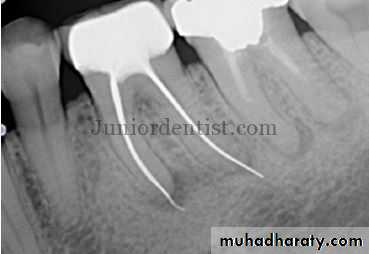

Typically, there are minimal or no changes in the radiographic appearance of the periradicular bone.With advanced irreversible pulpitis, a thickening of the periodontal ligament may become apparent on the radiograph, and there may be some evidence of pulpal irritation by virtue of extensive pulp chamber or root canal space calcification or even internal resorption

Radiographic changes may occur, ranging from a thickening of the periodontal ligament space to the appear-

ance of a periapical radiolucent lesion

Radiographs reveal presence of radiolucency with irregular enlargement of the root canal compartment